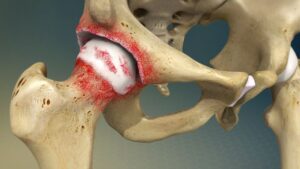

Avascular Necrosis (AVN)

Loss of blood supply to the hip bone leading to joint damage.